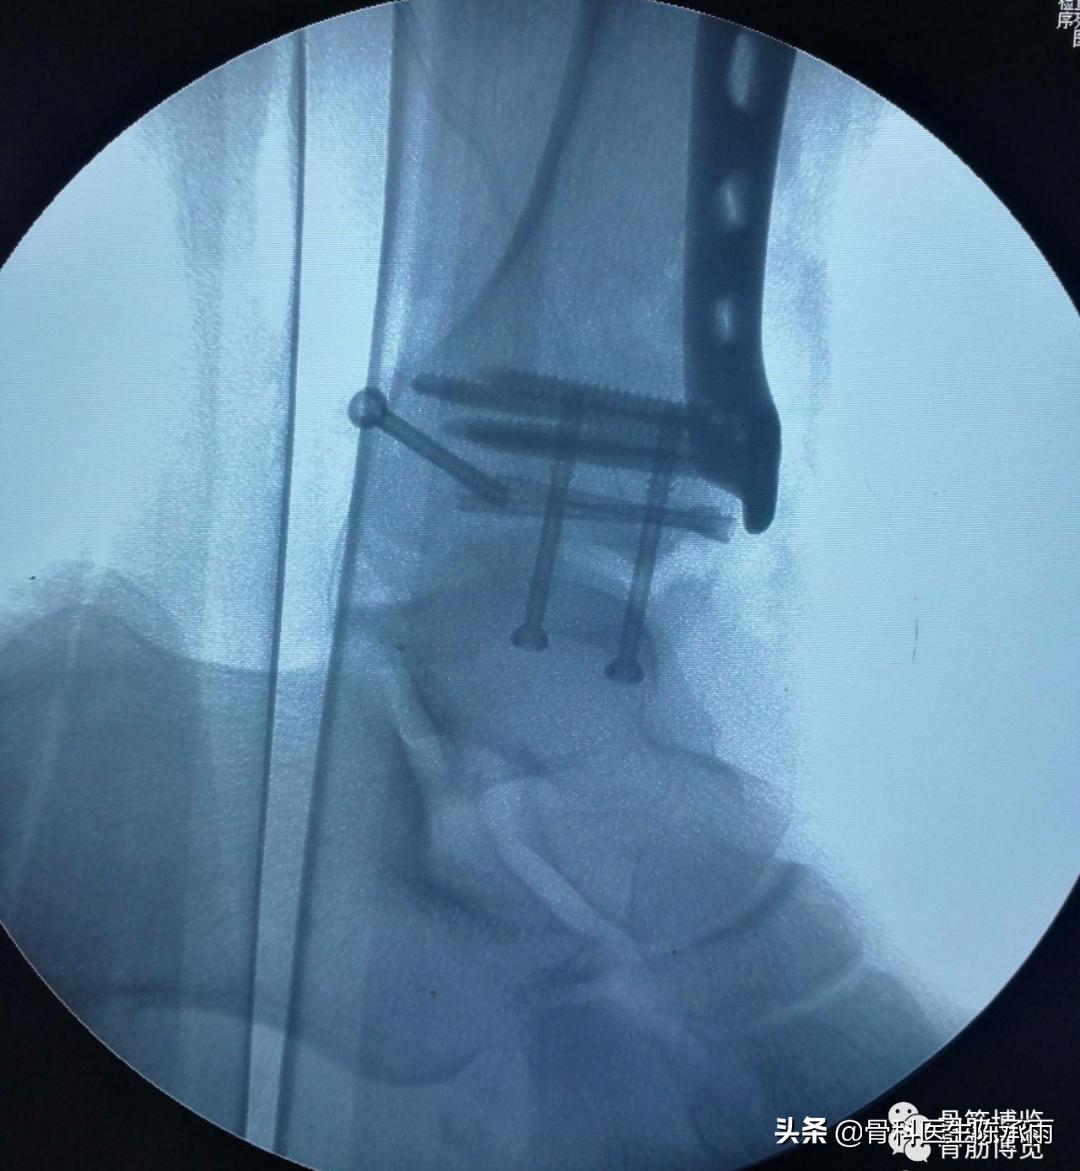

9、后踝骨折于腓骨长短肌后肌间进入显露,最后进行,新鲜骨折在另外三踝复位的情况下大多已经自行复位。可以用空心钉或后踝板固定。

10、如遇胫腓联合分离,同时可以拉力固定。但一般要求3个月内取出。

骨折固定满意。